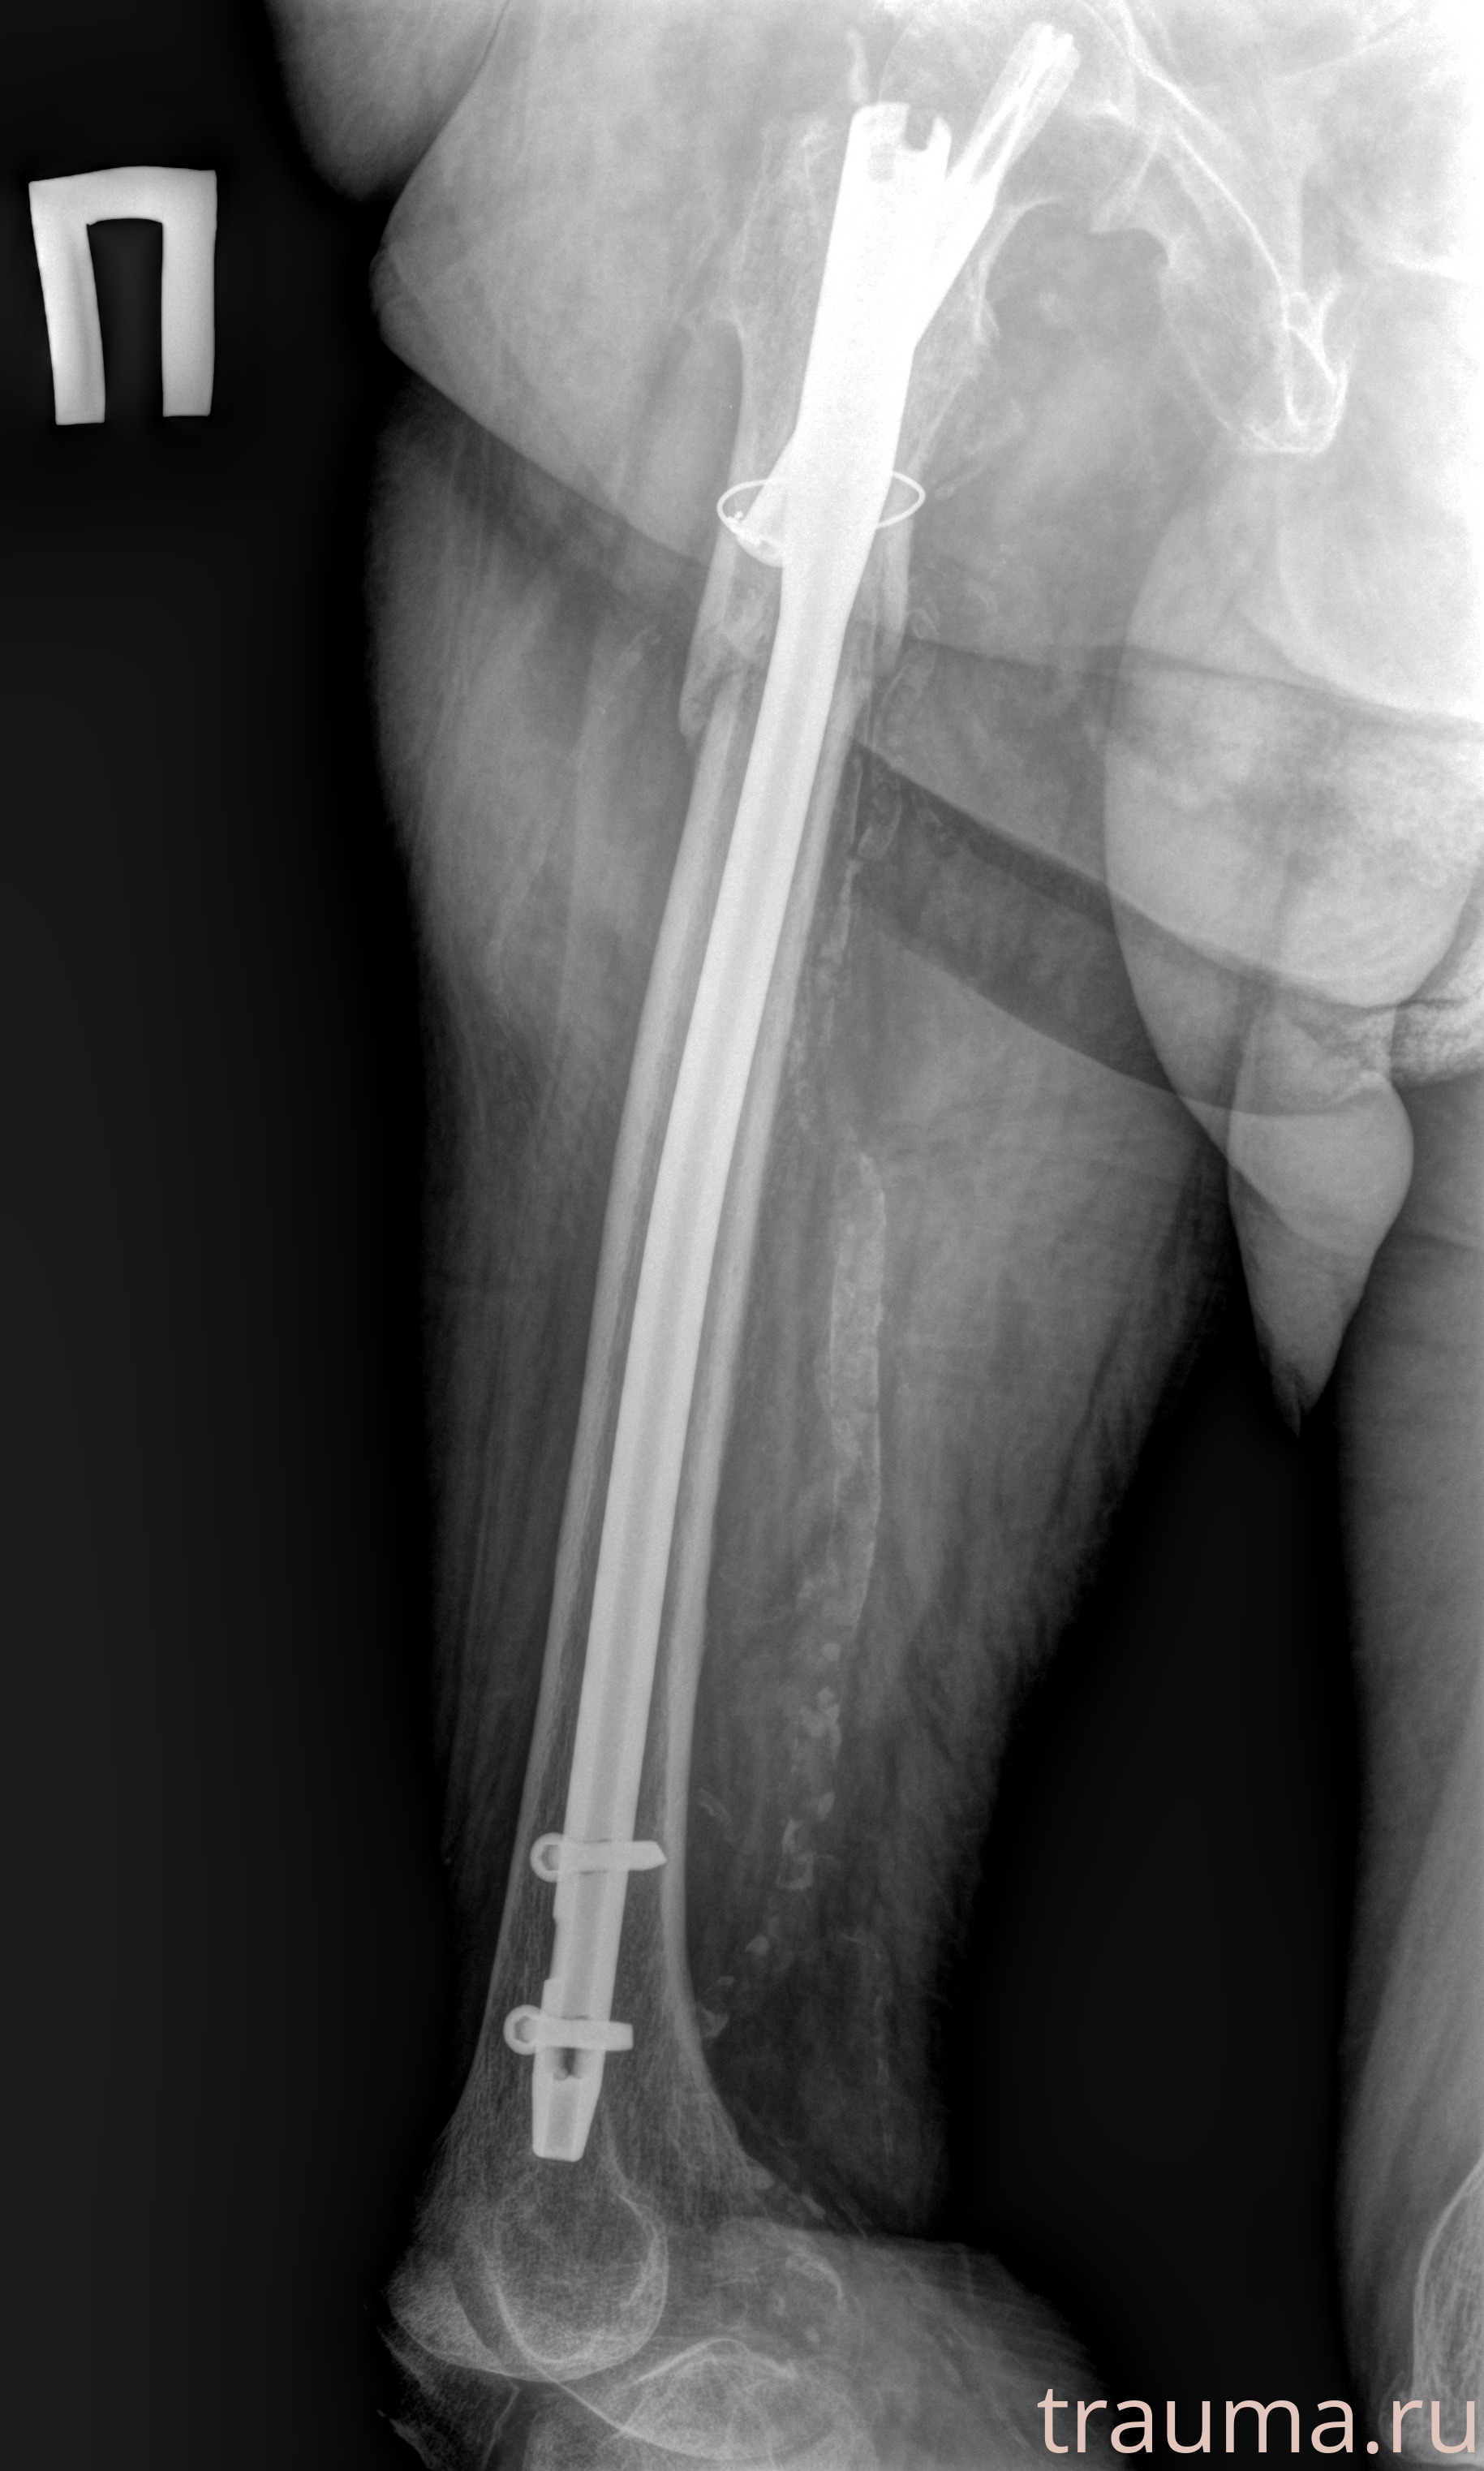

Рентгенограммы

Рентген на дому: по вашему адресу приезжает врач-рентгенолог, травматолог-ортопед с мобильным рентгеновским аппаратом, проводит диагностику травмы или заболевания, делает необходимые рентгенограммы, дает рекомендации по дальнейшему лечению. Получить качественные снимки в домашних условиях возможно благодаря уникальной методике, разработанной МосРентген Центром для института  Склифосовского